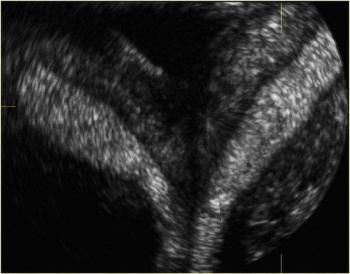

4D image of 29 weeks pregnancy, multiple anomalies: Clinch hand, omphalocoele, single atrium